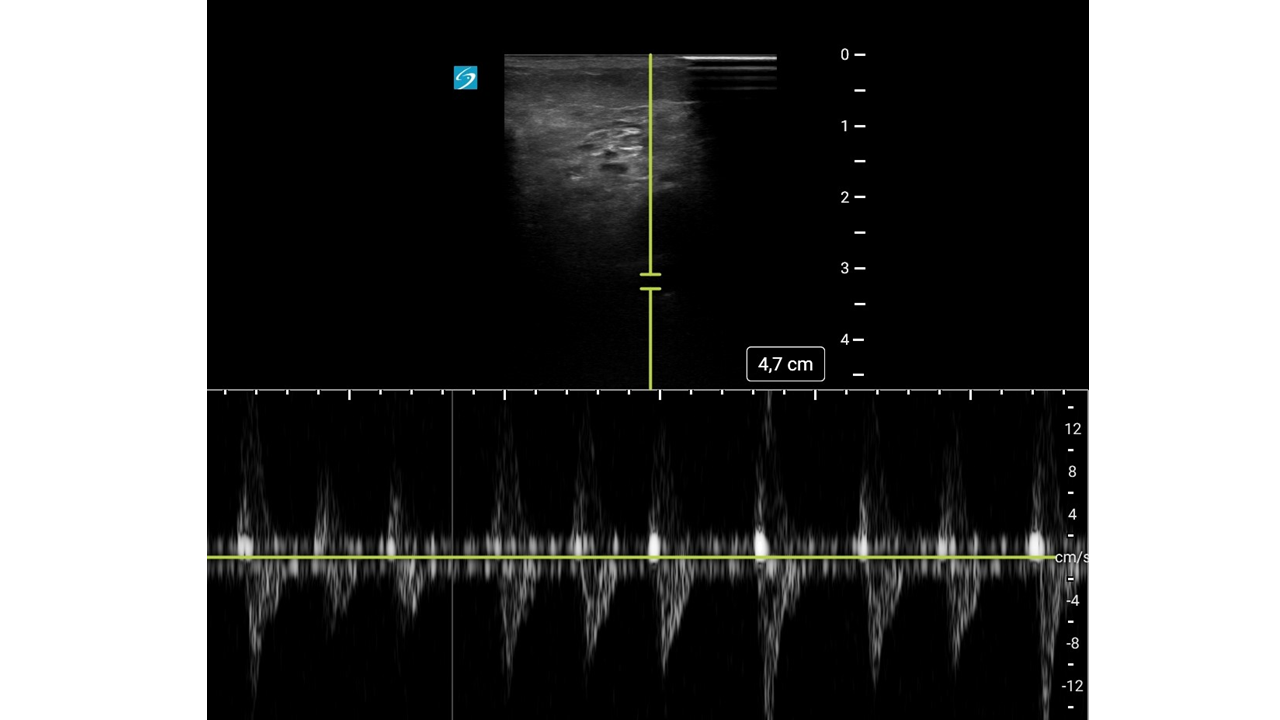

Con mejoría del dolor y pulso poplíteo dudoso, se duda del diagnóstico.

Con sospecha inicial de Isquemia Arterial Aguda (IAA), la mejoría clínica hace dudar abriendo el diagnóstico diferencial a una posible radiculopatía.

Con el diagnóstico de IAA se pauta analgesia, heparina de bajo peso molecular, posición de antitrendelenburg y se traslada a la paciente al Servicio de Cirugía Vascular de nuestro hospital de referencia, en cuyo ingreso se trata de forma conservadora con anticoagulantes.

Con sospecha clínica de IAA, la ecografía vascular es clave para confirmar el diagnóstico. Su curva de aprendizaje es rápida, se puede utilizar en cualquier punto del sistema y permite derivar al paciente a un centro útil evitando demoras potencialmente fatales.